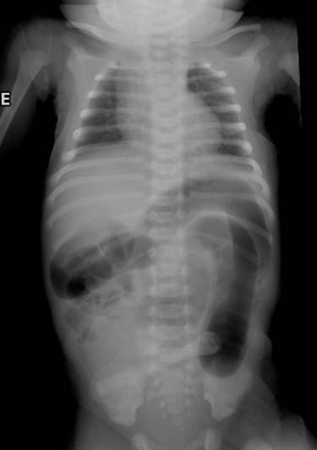

Abdominal x-ray of a neonate with abnormal stooling pattern and constipation. The dilated transverse and descending colon is suggestive of Hirschsprung's disease

From the collection of Dr KuoJen Tsao; used with permission